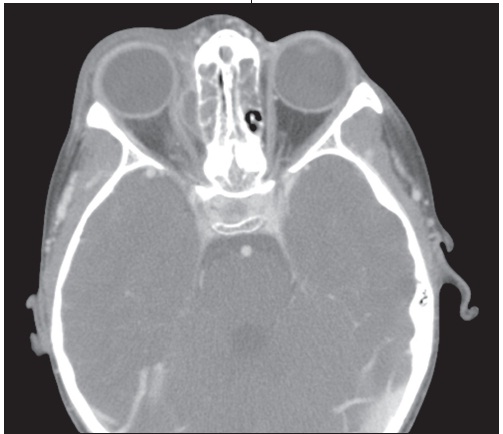

A 3-month-old infant was brought for evaluation after the sudden development of a tonic-clonic seizure that involved the left upper extremity.